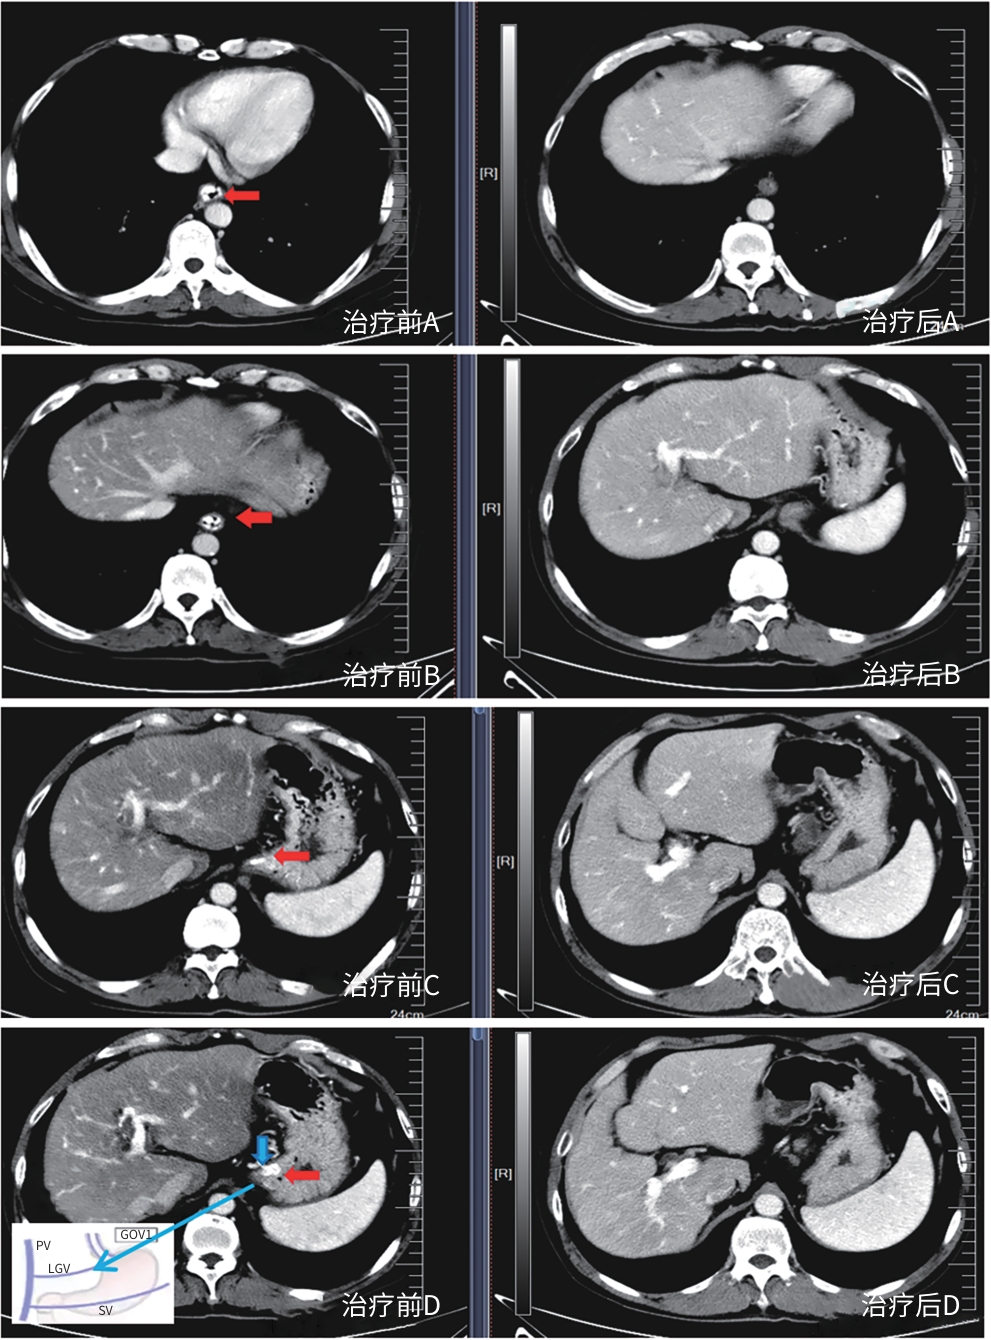

剩余肝体积不足的二期肝切除技术的应用现状与展望

宋书贤, 李云冬, 张钰清, 邹光旭, 李宽, 高红强

2025, 41(10): 2168-2173. DOI: 10.12449/JCH251031

摘要:

剩余肝体积不足是限制肝脏恶性肿瘤患者接受一期手术的关键因素。促进剩余肝体积增生以实现二期肝切除的技术包括门静脉栓塞术、联合肝脏分隔和门静脉结扎的二步肝切除术及肝静脉剥夺术。近年来,辅助性肝移植的应用进一步实现二期全肝切除。本文系统综述了上述技术的临床应用现状,并分析其优劣势,旨在为优化临床决策提供参考。